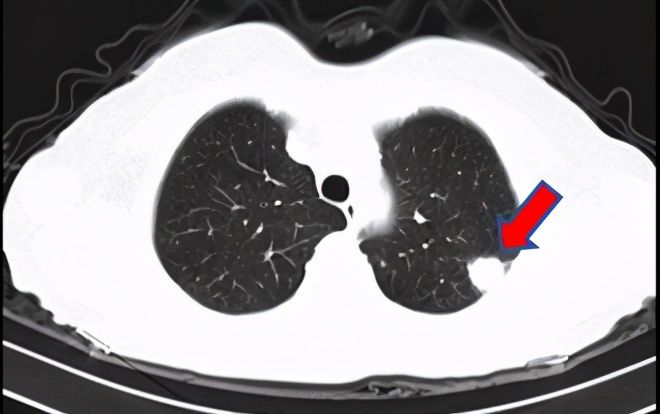

粗球孢子菌杨阿姨对健康非常重视,每年都体检。但今年的体检有点不妙:胸部CT发现左上肺有一个结节,而且经过随访还有增大的趋势。杨阿姨寝食难安,干脆一步到位去做了PET/CT,看到报告上说的“左肺上叶恶性肿瘤伴xxxx淋巴结转移和xxxx骨转移可能”,她五雷轰顶。但是感染病科医生说,没有病理确诊,还不能说一定是肿瘤,看片子还有良性疾病的可能。杨阿姨仿佛抓住了救命稻草,赶紧住院检查。